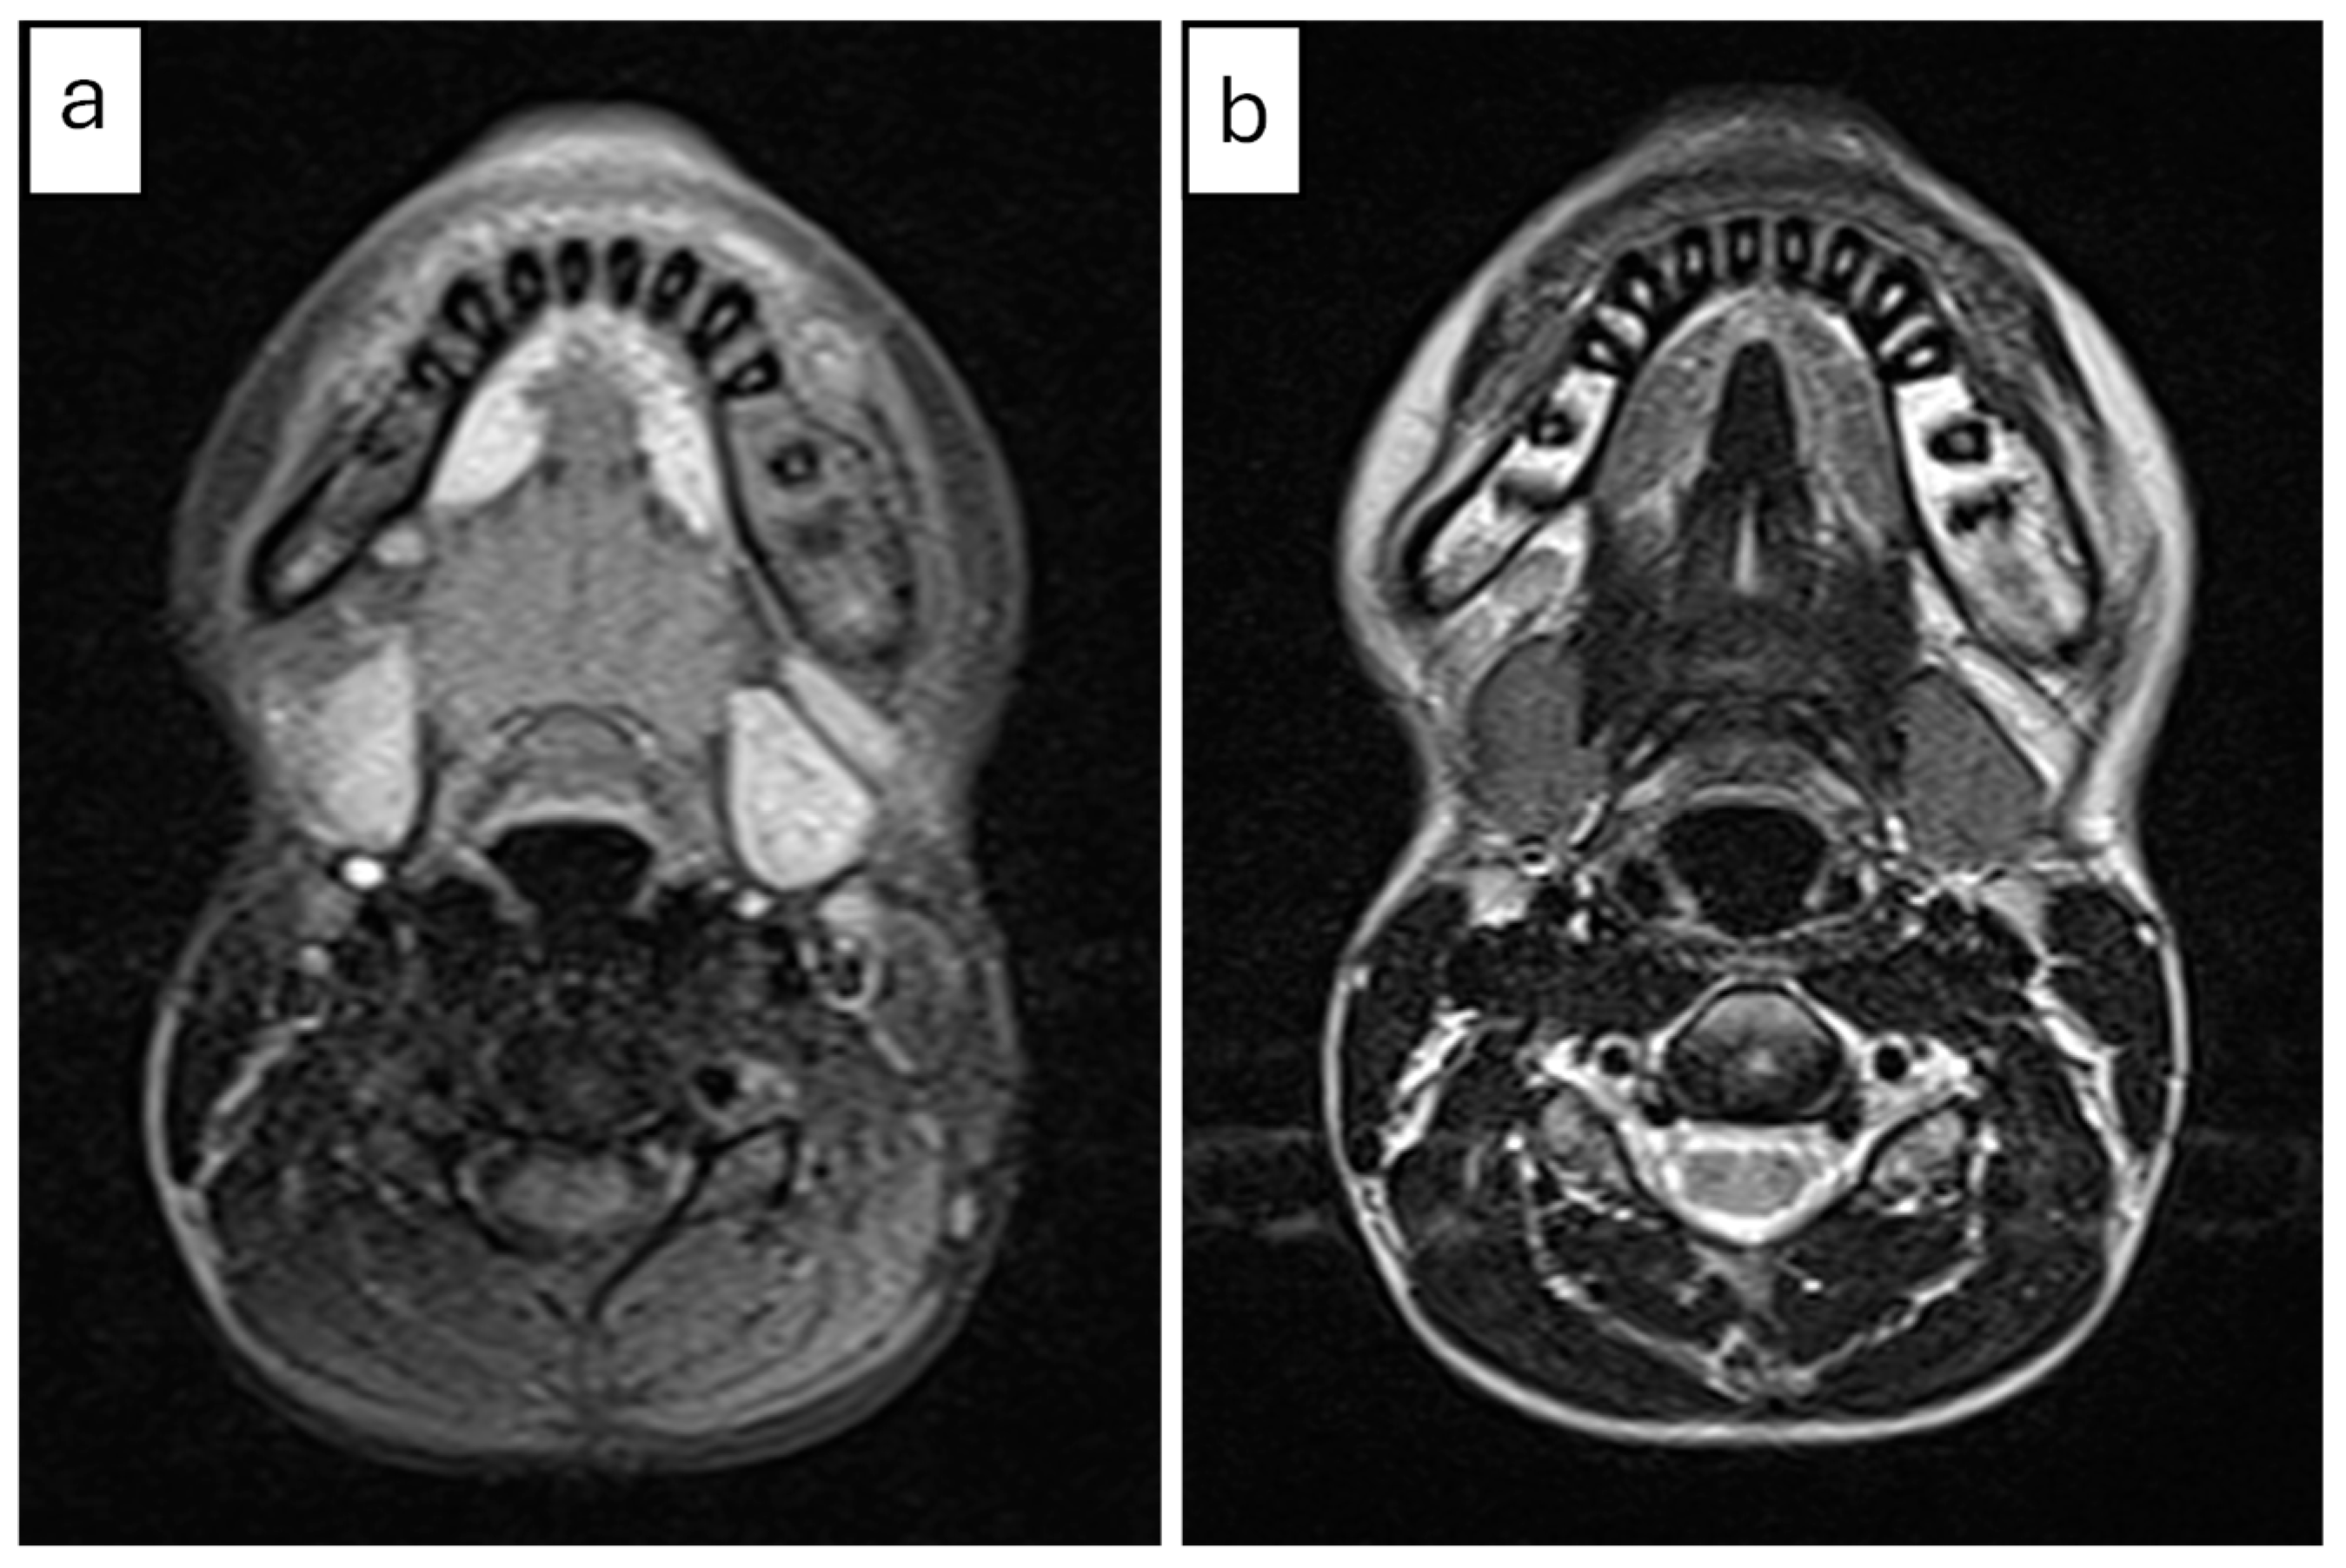

2.2.2. Radiographic Examination

| 2 | 9 | Right mandible (#33–#47, crossing midline) | Patchy sclerotic and radiolucent lesion, mandibular expansion, double cortex | Viable bone with osteoblastic rimming, no bacterial colonies | Multiple antibiotics, extractions, NSAIDs | CNO based on imaging, histology, and clinical course | NSAIDs only; progressive improvement | Gradual resolution with NSAIDs |